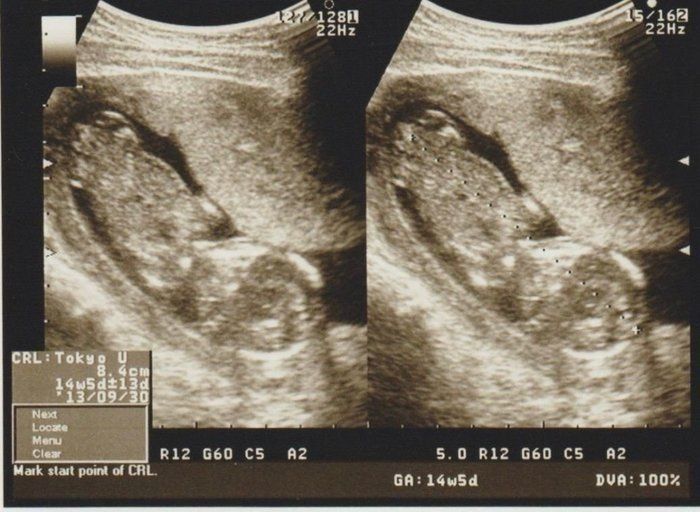

育児日記 新米パパの記録 妊娠14週目の超音波写真

14週3日目 そろそろ飽きてきた はなjr が生まれるまでの日々